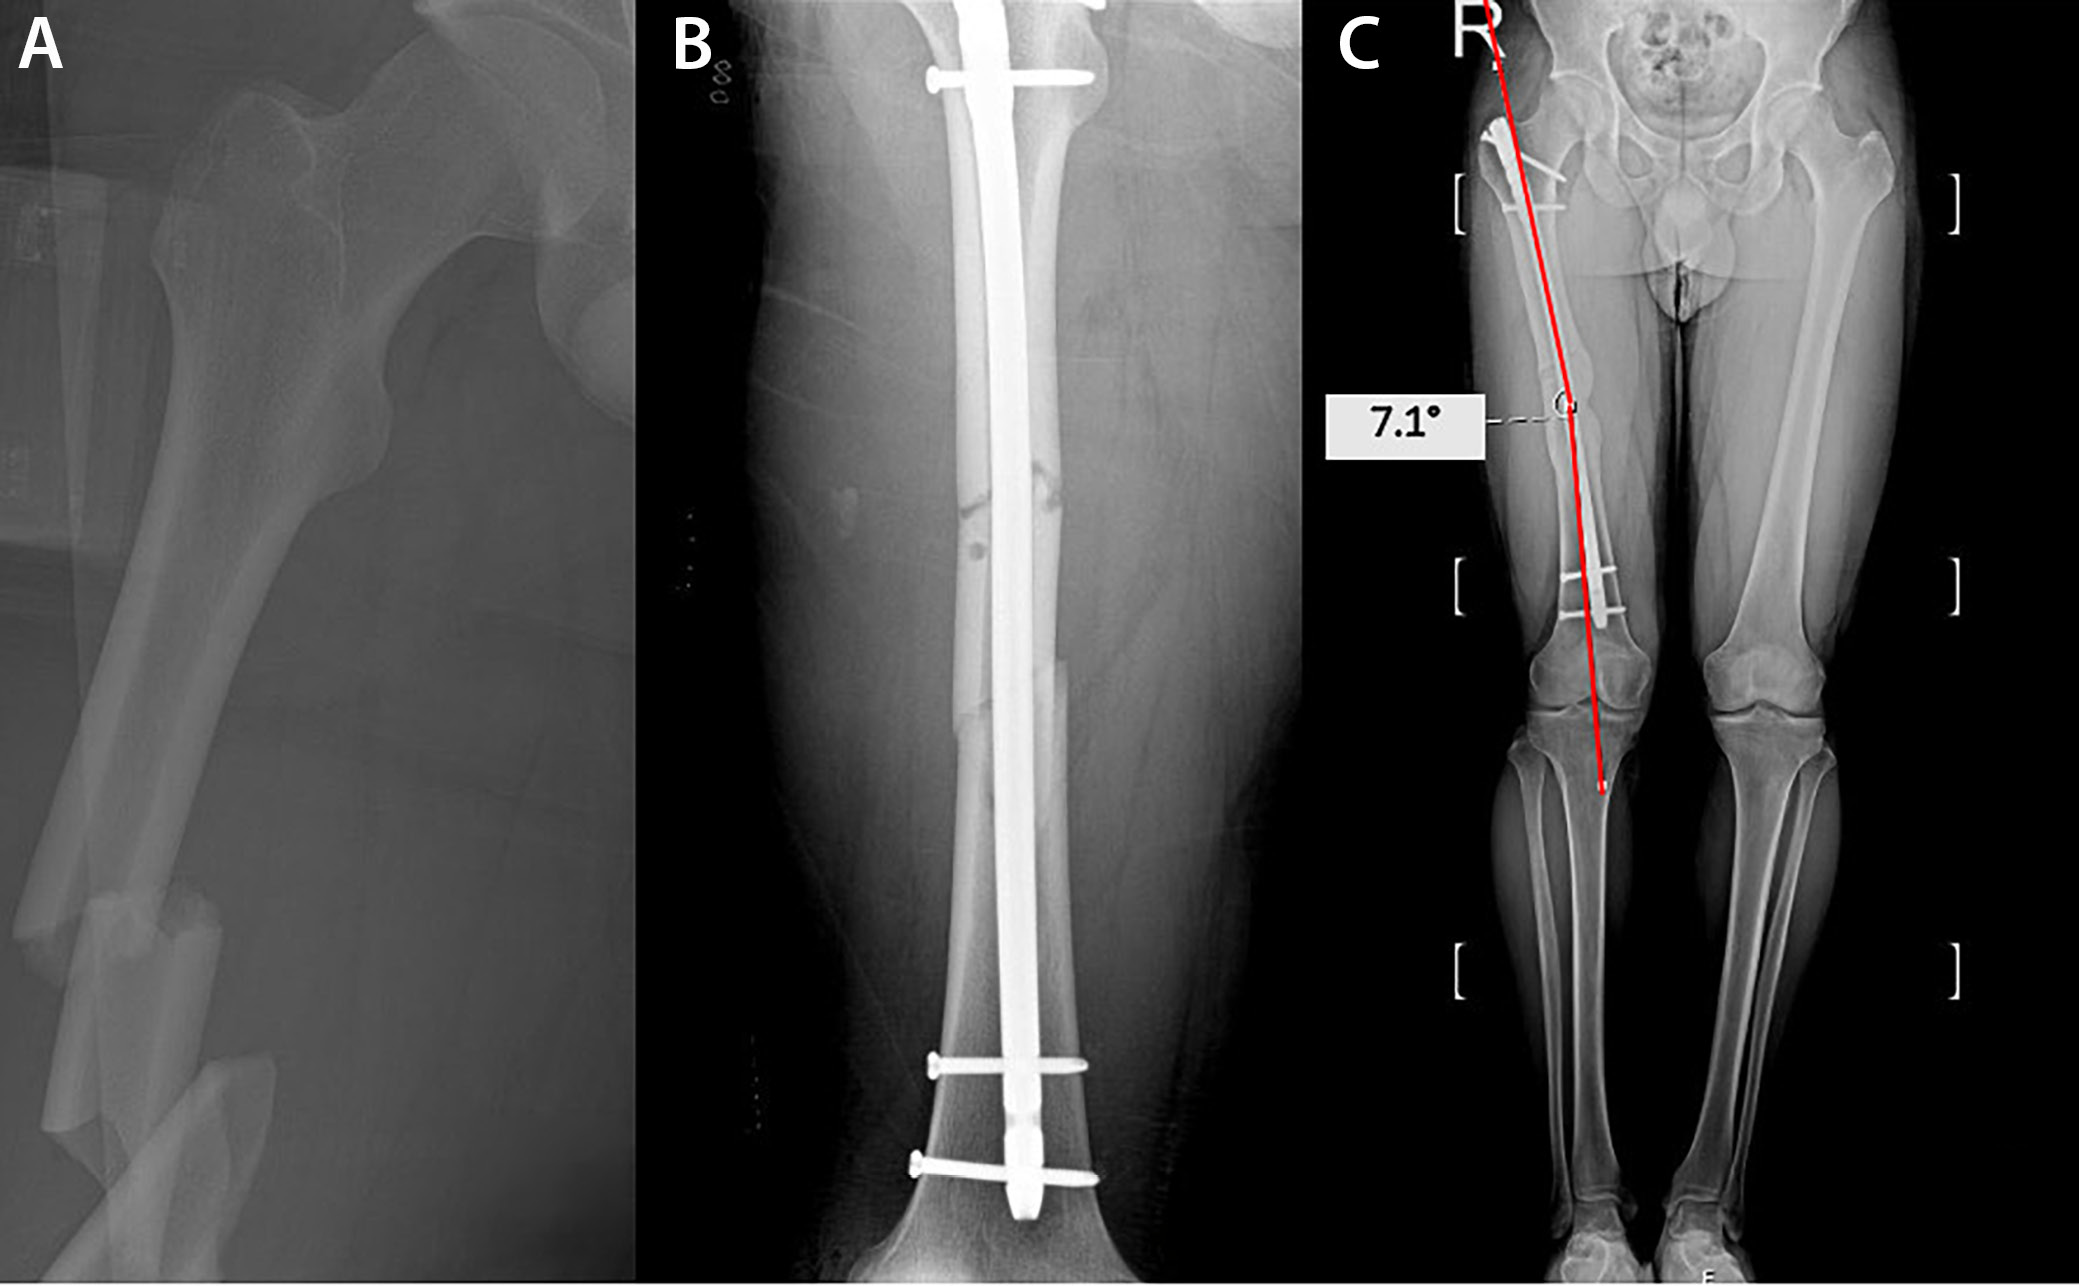

Orthoroentgenograms were used to assess femoral length discrepancies, coronal plane angulations (varus/valgus) at the fracture line, mechanical lateral distal femoral angle (mLDFA), mechanical medial proximal tibial angle (mMPTA), and postoperative lower extremity mechanical axis angle (MA), and to compare the sizes of the lesser trochanters on both sides to detect rotational deformity (Figure 1, Figure 2, Figure 3). Coronal plane deformity of the femur was evaluated by drawing one line from the fracture site to the proximal center of the medullary canal and another line from the fracture site to the midpoint of the distal femoral articular surface. The angle between these 2 lines was then measured (Figure 1C, Figure 2C).

Patients were divided into 2 groups based on the coronal plane angle measurements of the femoral fracture line obtained from orthoroentgenograms: group A, with angulation less than 5° (n = 100, 83.4%), and group B, with angulation of 5° or more (n = 20, 16.6%). In group B, 6 patients (30%) exhibited varus deformity, while 14 patients (70%) displayed valgus deformity. The median coronal plane angle was 1.14° (Q1 = 0.5, Q3 = 2) in group A and 5.74° (Q1 = 5, Q3 = 6.2) in group B.